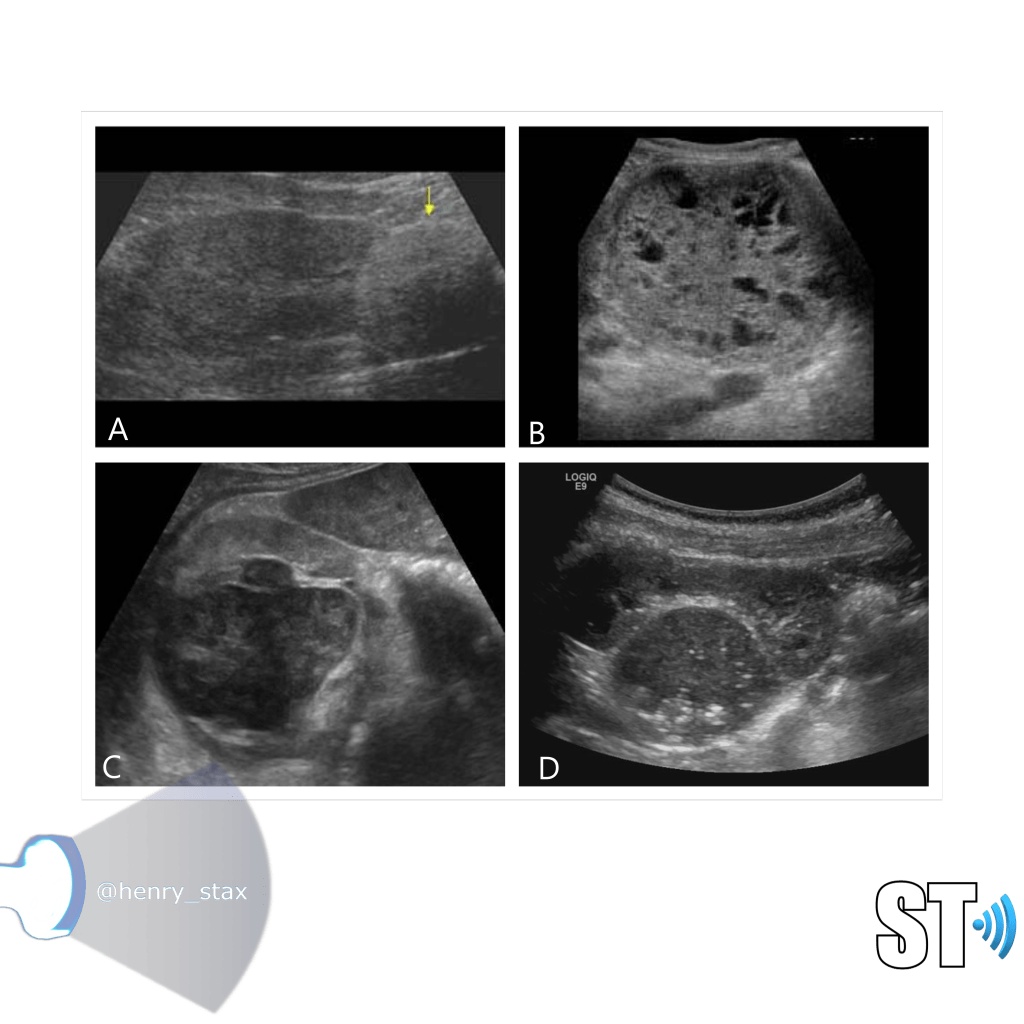

MCDK

Multicystic Dysplastic Kidney results from a ureteral obstruction before the 8th or 9th week of fetal development. MCDK is usually diagnosed prenatally or shortly after birth if an ultrasound is ordered. The affected kidney is non functioning and is replaced by cysts of various sizes and connective tissue.

- Malformation of the kidney during fetal development

- Multiple cysts

- Contralateral UPJ obstruction is found in 3% to 12%

- Usually unilateral (bilateral form is usually fatal)

ARPKD

ADPKD

In Autosomal Dominant Polycystic Kidney Disease (ADPKD) the kidneys are normal at birth with cysts developing overtime. By age 30 years, approximately 68% of patients will have visible cysts by ultrasound. Eventually, virtually all patients develop cysts. The disease is transmitted in an autosomal dominant pattern, meaning you only one abnormal gene from one parent.

One abnormal gene from one parent

- Adult

- 4-10% of all cases of ESRF

- Kidneys appear normal early on

- Liver, pancreas and spleen cysts